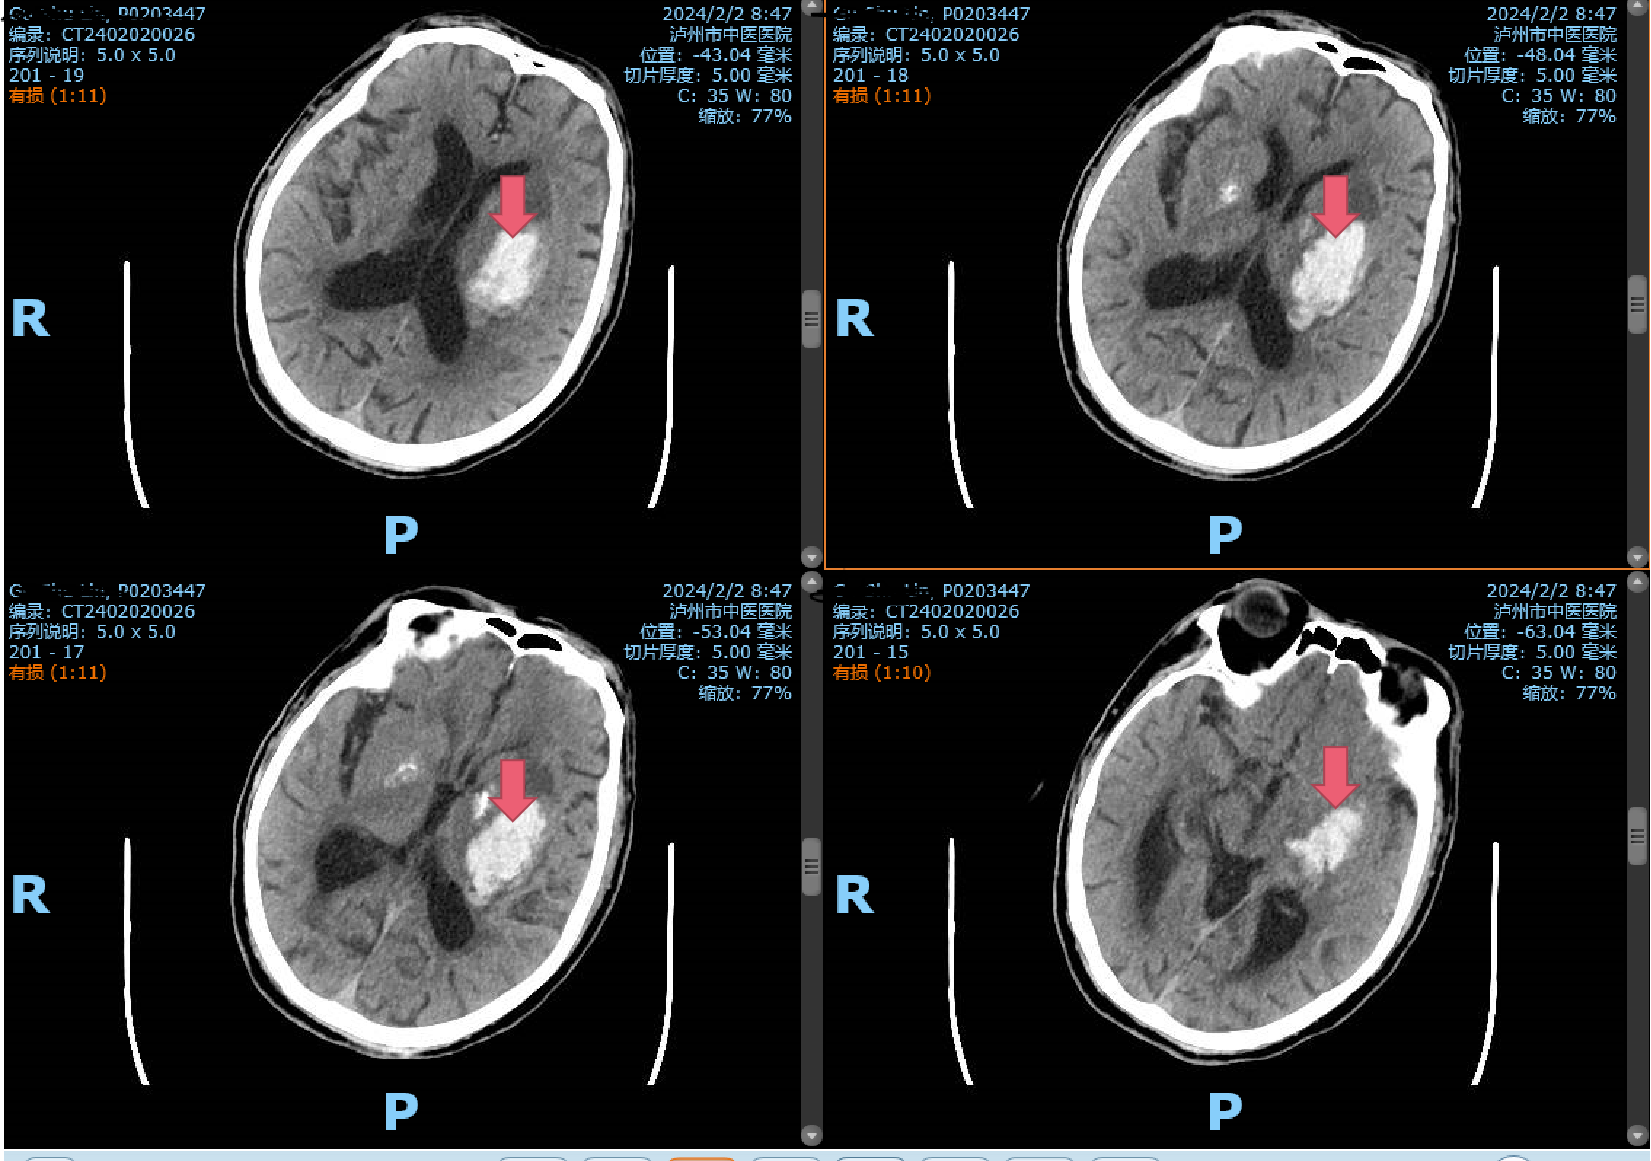

2月2日一早,一陣急促的響鈴聲打破了清晨的寧?kù)o,一位年逾古稀的辜先生在洗澡時(shí)突發(fā)一側(cè)肢體無(wú)力,家屬見(jiàn)狀不知所措,焦急萬(wàn)分,情急之下將患者背下樓,直接送入瀘州市中醫(yī)醫(yī)院急診科!時(shí)間第一,生命至上?;颊呷朐汉笾苯咏?jīng)急救通道,完善頭顱CT,提示腦出血,病情危重,立即及時(shí)、安全地送到了市中醫(yī)院重癥監(jiān)護(hù)室,并...